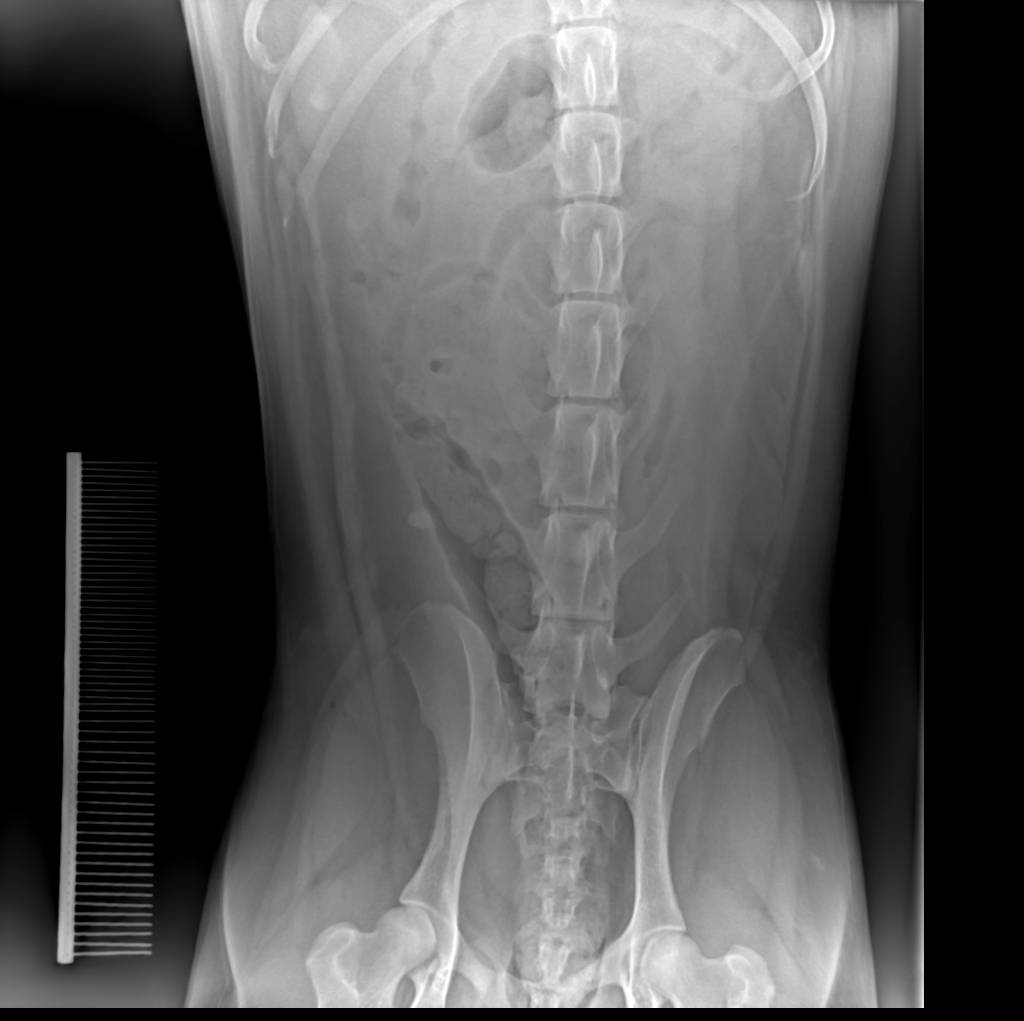

犬呕吐怀疑胃肠梗阻X线造影前正位平片2